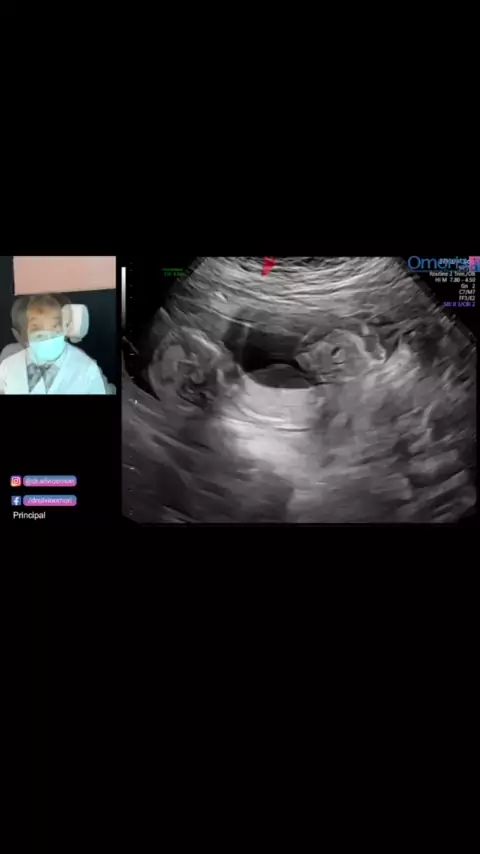

gravidez com DIU!! #diu #👶🏻bebe #Mae #ultrassom #gravidez